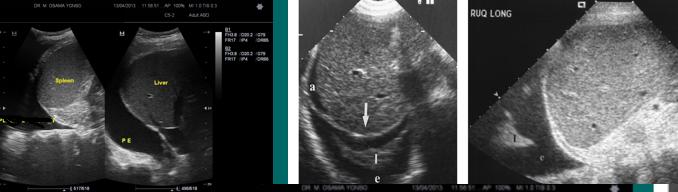

ascites (fluid collection)

pleural effusion (fluid collection)

hematoma (fluid collection)